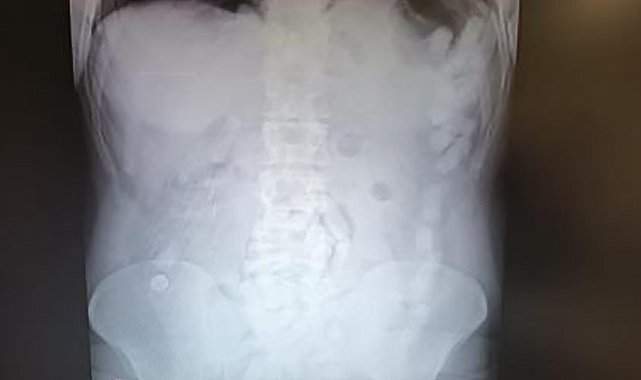

Kayseri'de midesinde 100 kapsül içinde 729 gram uyuşturucu maddeyle yakalanan şahsa 12 yıl 6 ay hapis cezası verildi.4 Mayıs 2024'te Kayseri İl Emniyet Müdürlüğü Narkotik Suçlarla Mücadele Şube Müdürlüğü ekipleri, yabancı uyruklu A.H.'nin ülkeye giriş yaparak üzerindeki uyuşturucu maddeleri Kayseri'ye getireceğini tespit etti. Şahsı takibe alan ekipler, yerini tespit ettikten sonra operasyon düzenledi. Kayseri Şehir Hastanesinde ultrason çekimi ile yapılan kontrolde şahsın midesinde çok sayıda kapsül olduğu tespit edildi. Yapılan operasyonla şahsın midesinden çıkarılan 100 adet kapsülün içerisinde 729 gram uyuşturucu madde ele geçirildi. İşlemlerinin ardından adliyeye sevk edilen şüpheli, çıkarıldığı mahkemece tutuklanarak cezaevine gönderildi.12 yıl 6 ay hapis cezası verildiBugün 8. Ağır Ceza Mahkemesi'nde görülen karar duruşmasında hakim karşısına çıkan A.H., savunmasını Türkçe yaparak, bir kere bile elinin uyuşturucuya değmediğini, midesine zorla koyduklarını belirterek, pişman olduğunu ve Türk milletinden özür dilediğini söyledi. Sanığın avukatı ise, müvekkilinin etkin pişmanlıktan yararlandığını, kolluk güçlerine yardımcı olduğunu belirterek, ele geçirilen uyuşturucu miktarını yutarak getirmesinin hayatın olağan akışına ters olduğunu dile getirdi.Yapılan yargılama sonucunda yabancı uyruklu A.H.'ye 'uyuşturucu ticareti yapmak' suçundan 12 yıl 6 ay hapis cezası verildi.